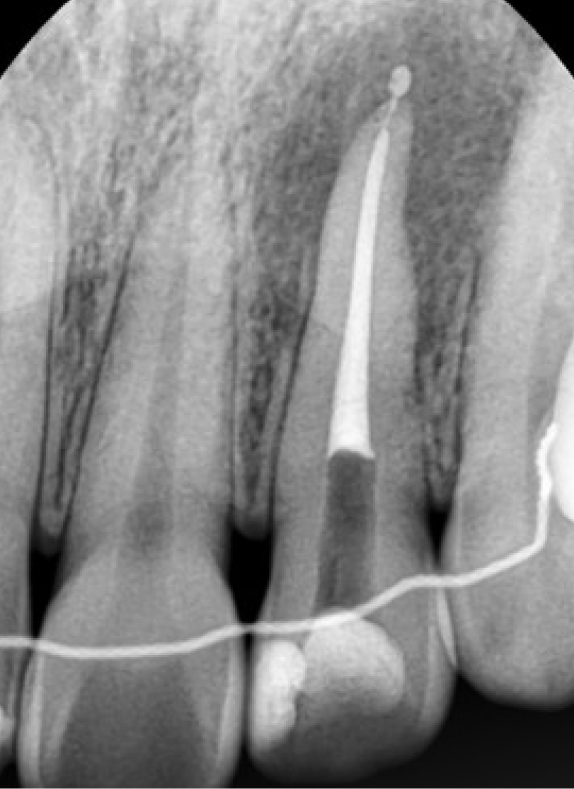

엑스레이 촬영 결과,

해당 치아의 치수(신경)가

이미 괴사된 상태였고

치아 뿌리 끝(치근단) 주변으로

어두운 음영이 보였습니다.

1단계. 근관치료(신경치료)

먼저 괴사된 신경 조직을 제거하고

치근단 부위의 염증을

깨끗하게 정리해주는

근관치료를 진행했습니다.